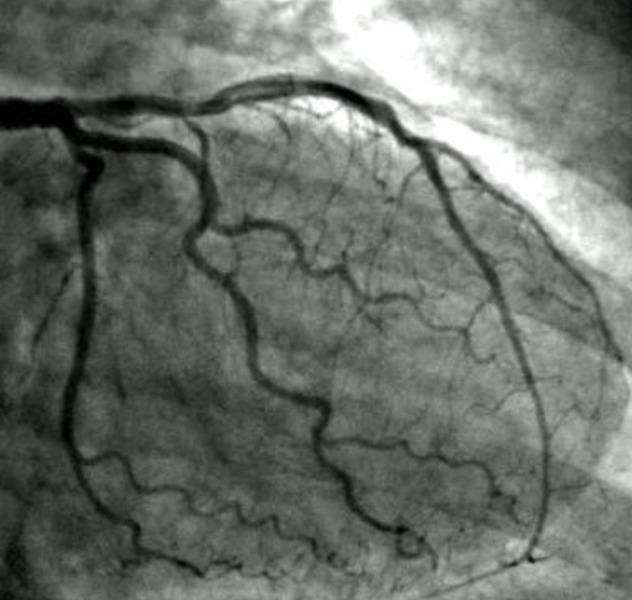

Image Gallery

Pictures That Speak